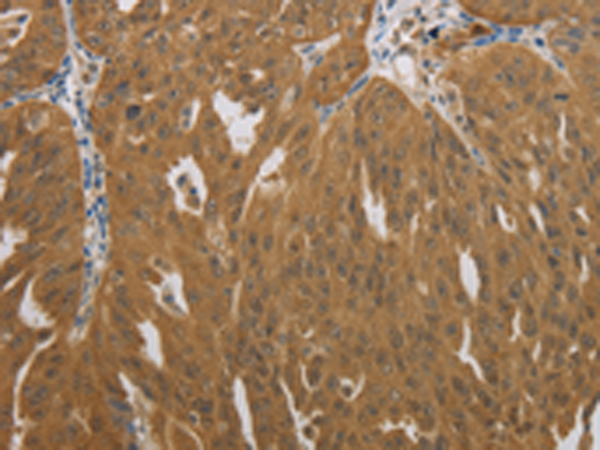

分类: 科研抗体货号: P11264别名: λlight chain应用: WB,IHC反应种属: Human